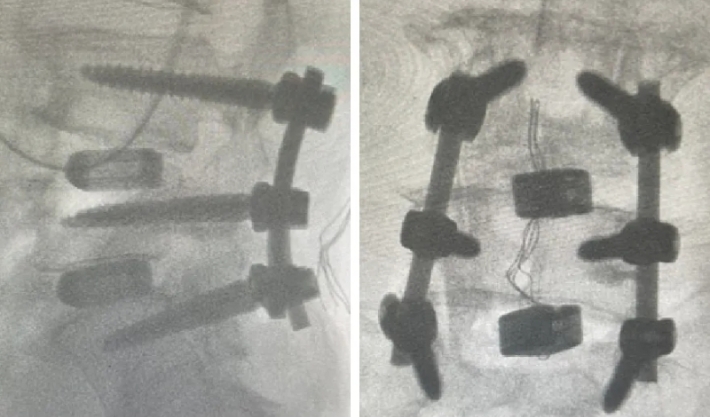

近日,beat365中文在线官网第六附属医院(新疆维吾尔自治区骨科医院)脊柱外三科在医疗技术上取得新的突破,成功为两位腰椎手术患者利用3D打印融合器实施了腰椎椎体间融合术,患者术后恢复良好。

随着人口老龄化趋势不断加剧,腰椎间盘突出症、腰椎管狭窄症、腰椎滑脱等已成为常见的退行性脊柱疾病之一,严重影响中老年人的生活质量和身心健康。腰椎椎体间融合术是解决退行性脊柱疾病的常用手术方式之一。然而,在老年人骨质疏松、骨含量低的情况下,容易发生植骨融合失败的后遗症。3D打印融合器能有效解决这一问题。这两例手术中所使用的融合器,是通过3D打印技术制造的一种新型的多孔钛合金椎间融合器,它的微观和宏观结构模仿了人体椎体的天然骨小梁,更加贴合人体结构。同时,进一步优化了材料表面,使其具有更好的生物相容性和成骨活性,能够帮助新生骨快速长入融合器,加速愈合。该融合器还很适合微创手术,不需要再植入自体骨或其他骨修复材料,不仅提高了治疗效果,还减少了患者的手术创伤。